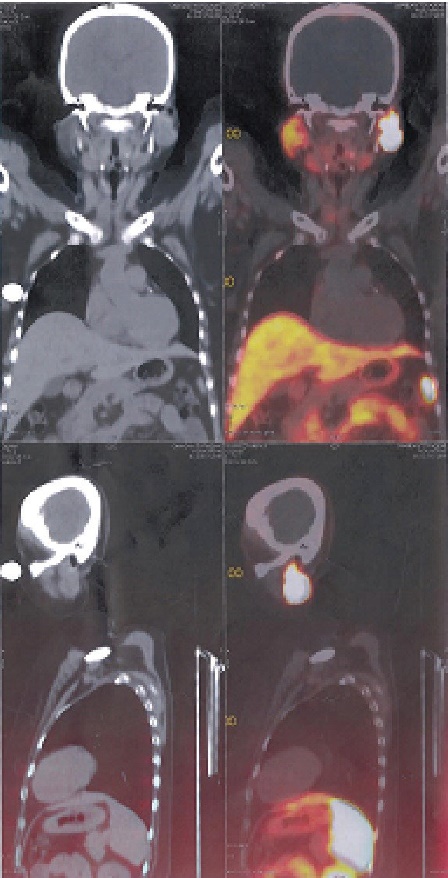

Radiological studies showed bilateral tibial shaft fractures, multiple fractures in bilateral tarsals (Figures 1 to 3). A PET Scan showed multiple insufficiency fractures of bilateral tibia, neck of right femur, metacarpal bones and scapula (Figures 4 to 7).

Figure 4.PET scan showing uptake over fracture part.

Figure 5.PET scan showing fracture of ribs.

Figure 6.PET scan showing fracture of tibial shaft.

Figure 7.PET scan showing multiple fractures.

Since the parotid tumour also has a mesenchymal component, it was thought to be a source producing FGF23. (68)Ga-DOTATE scan was done which showed increased uptake over left parotid, SUV (Standard uptake values) max – 97.5, other areas, had normal physiological uptake (Figure 8).

Click here to download Figure 8Figure 8.(68)Ga-DOTATE scan showing coronal and sagittal view of mass in left parotid.

For tumour localisation, imaging modalities such as X-ray, CT and MRI can be used. Some tumours express surface somatostatin receptors. Somatostatin receptor PET scan is used as a diagnostic tool in refractory cases. In our patient Somatostatin receptor PET scan was used as nuclear imaging method. Radiolabelled octreotide was injected in a patient and whole body follow images were taken. Tumours that have surface somatostatin receptors bind to the octreotide and light up images.

TIO is an acquired disorder of renal phosphate wasting that is associated with tumour. Patients with TIO present with hypophosphataemia with inappropriately suppressed 1,25 (OH)2 D concentration. Clinical symptoms include gradual onset of muscle weakness, fatigue and bone pain, especially for ankles, legs, hips and back. Insufficiency fractures are common and proximal muscles weakness can become severe enough for patients to require wheel chair or they become bedbound. This case highlights the importance of measuring serum phosphorus and phosphate clearance in patients with unusual musculo-skeletal pain and myopathic weakness. (68)Ga-DOTATE scan helps in localization of such a tumour and surgical resection can lead to total cure.